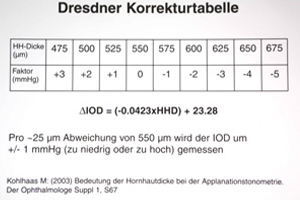

Die Messung der Hornhautdicke spielt bei der Glaukomdiagnostik eine entscheidende Rolle. Die Dicke der Hornhaut hat einen Einfluss auf die Messung des exakten Augeninnendrucks. Aus verschiedenen Untersuchungen ist bekannt, dass gerade bei Glaukompatienten die Hornhautdicke von der normalen durchschnittlichen Dicke von 550um abweicht. Weichen die Werte der Hornhaut deutlich ab, muss das Messresultat nach unten oder oben korrigiert werden (Dresdner Tabelle).

Bei einer dickeren Hornhaut ist der Augeninnendruck zu hoch, bei einer eher dünnen Hornhaut wird dieser aber unterschätzt. Fehlmessungen können hiermit erkannt werden und in der Diagnostik und Therapieplanung Berücksichtigung finden.

Hornhautdickenmessung